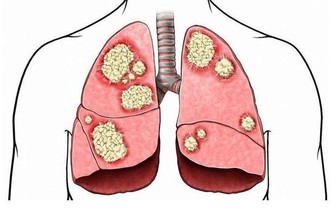

●肺經一通,感冒不來!肺經到底在哪裡?知名的中西醫師林燦城,節目中當場畫給你看!還有一套拍打肺經運動,促進肺部氣血循環,預防感冒!